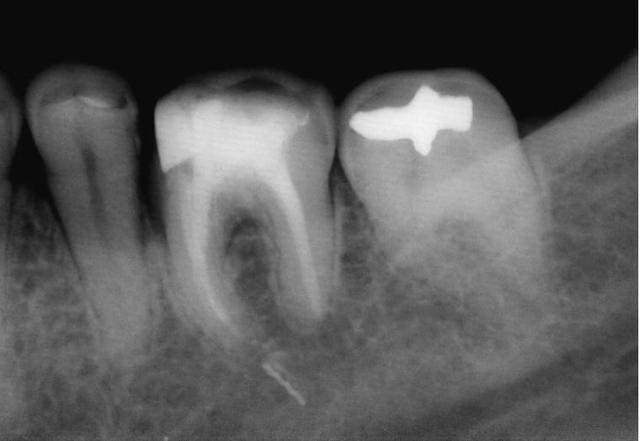

Voici un cas de fracture compacteur.

Utiliser un mac spaden dans ce genre de cas était une bêtise.

Aprés beaucoup d'efforts pour perméabliser les 2 cannaux et les préparer, c'est trop dommage de gacher le résultat en cassant un compacteur.

Cela ne m'a pas gêné pour desobturer et faire l'empreinte pour l'inlay-core, mais la condensation de la gutta au niveau apical n'a pas été terrible.

C'est d'ailleurs un des cas qui m' a décidé à utiliser de temps en temps le thermafill.